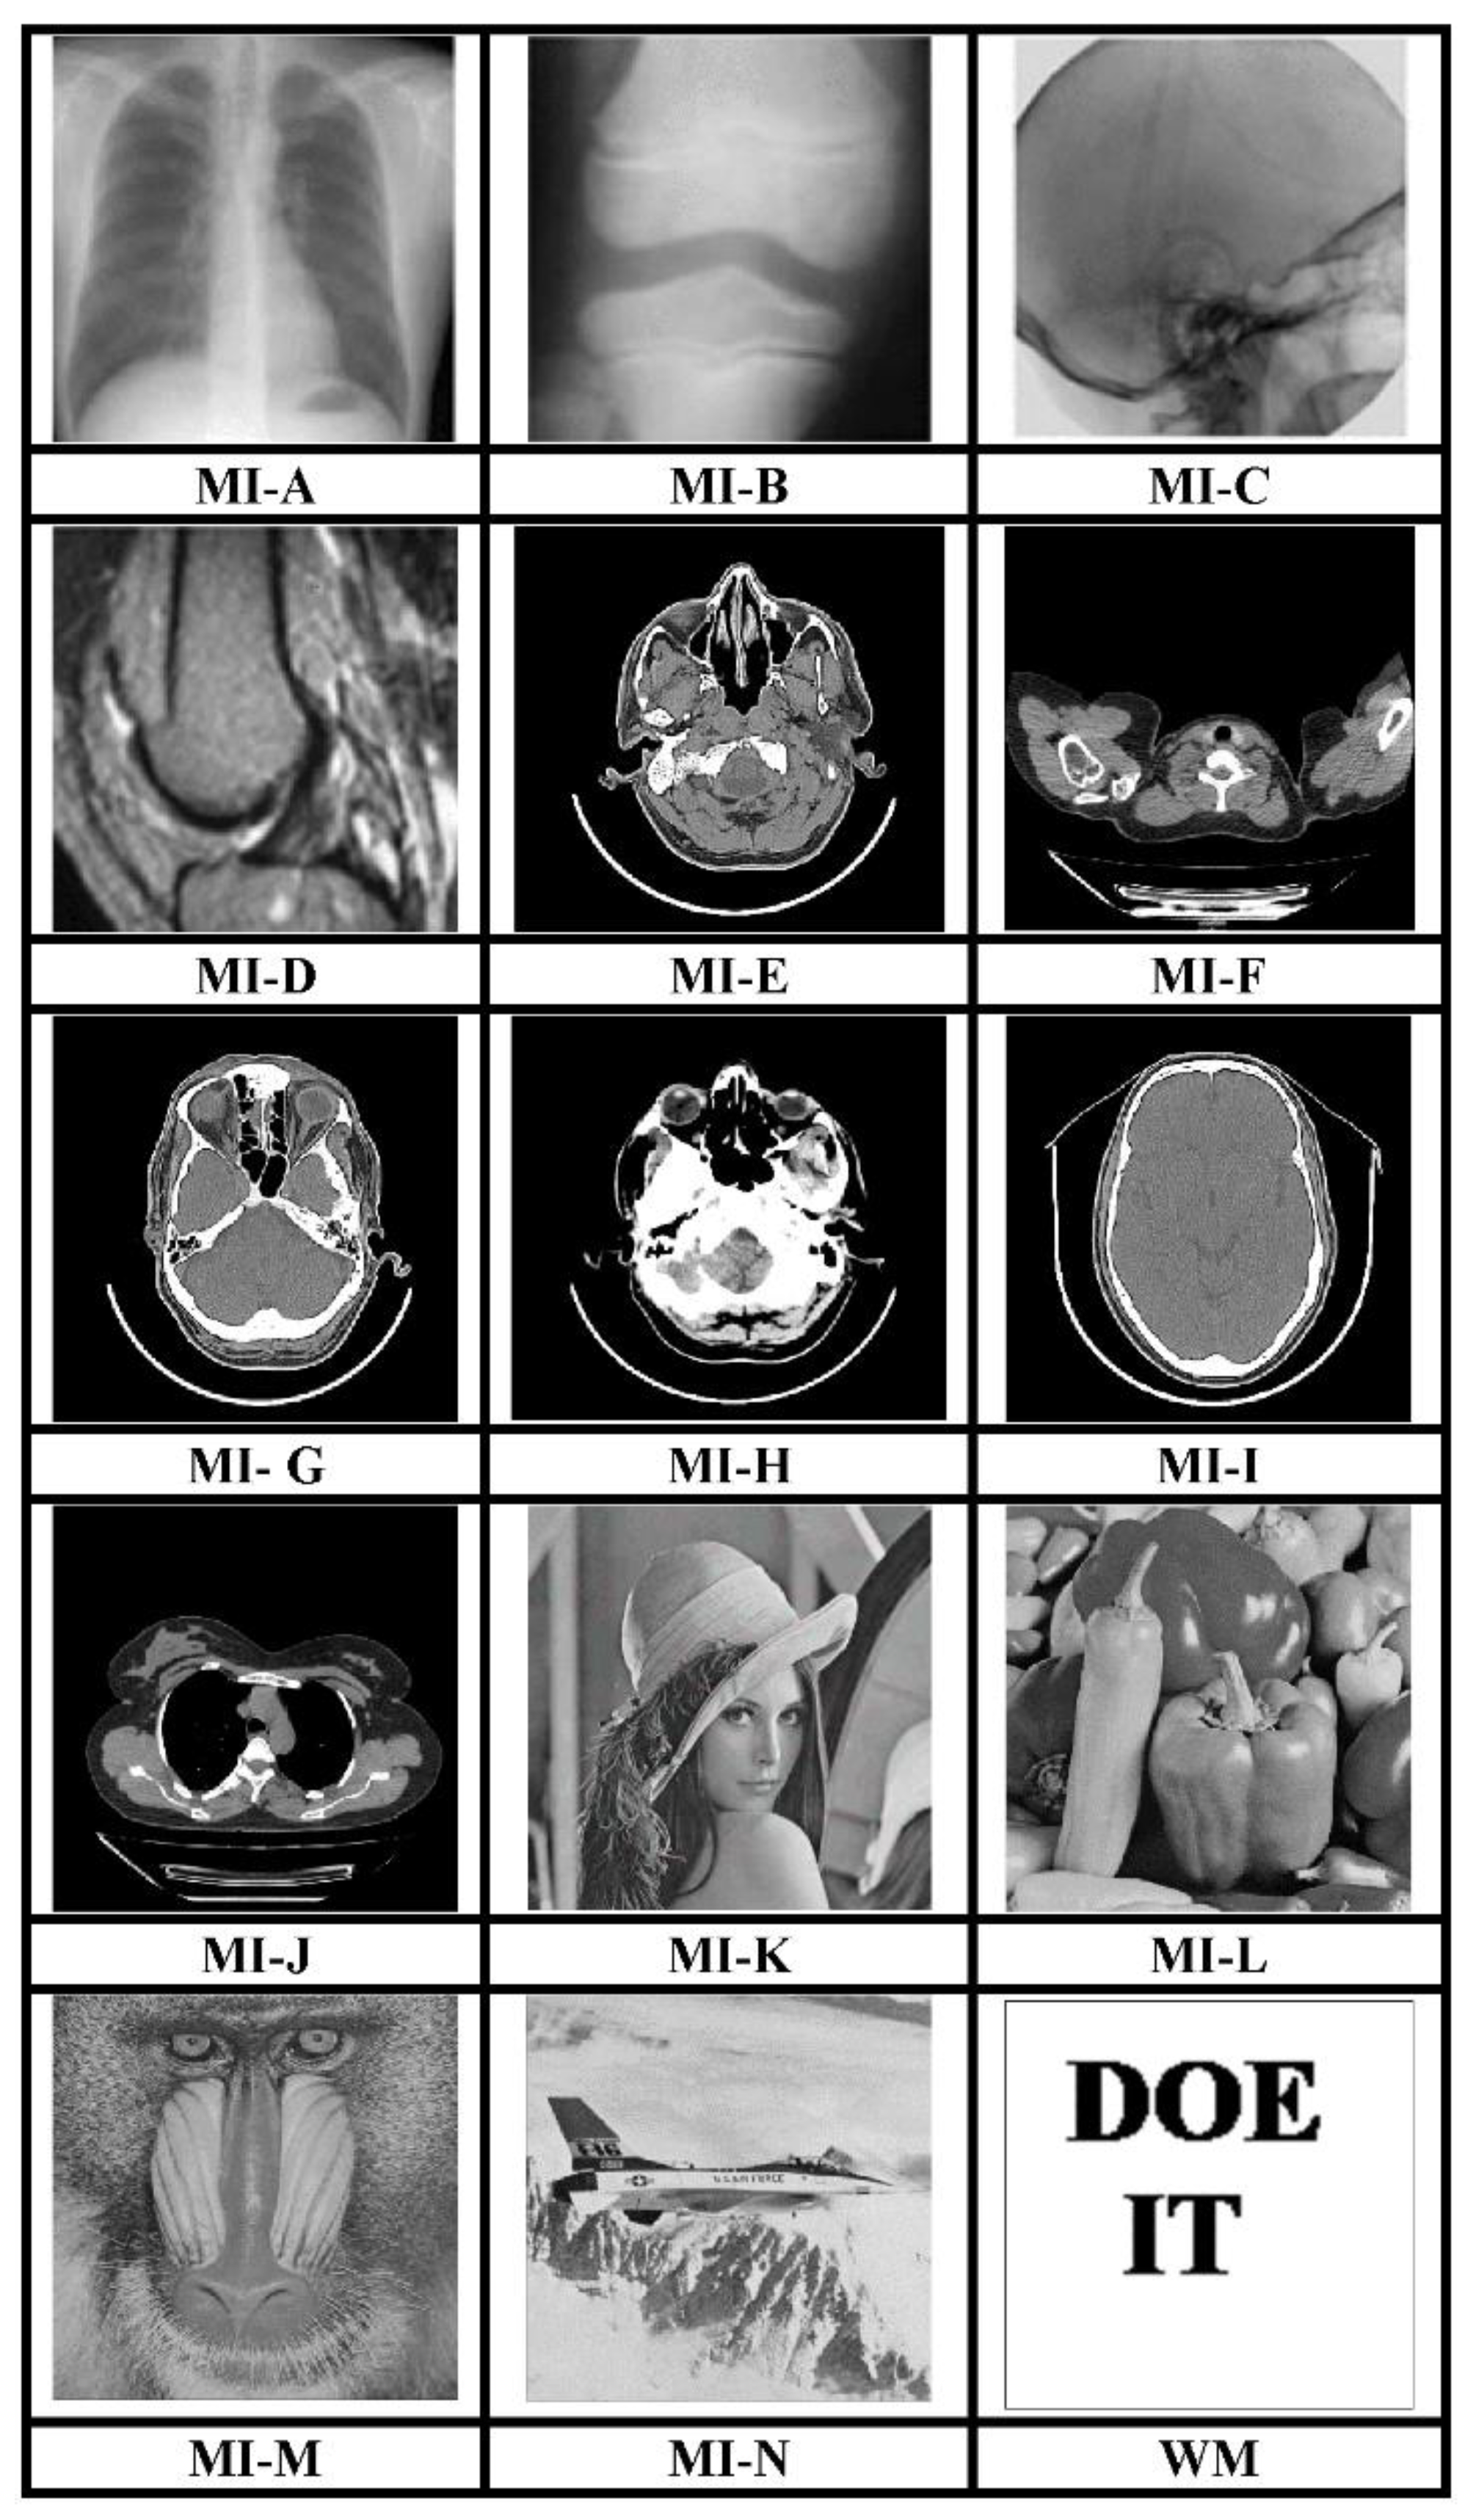

4. Experimental Results

The MATLAB R2017a platform has been utilized for carrying out the experimental investigations for different gray-scale natural and MI. Both types of images that have been used for testing have dimensions 512 × 512. We have conducted experiments using a 64-bit Windows 10 Operating system with an i5 processor, 8 GB RAM, and 2.40 GHz clock speed. The different images, as well as a logo as WM, have been represented in Figure 3. The binary WM employed for authentication purposes has a 128 × 128 size. The technique is evaluated for a payload of 196,608 bits or 0.75 bits per pixel (bpp). The scheme reports an average encryption speed close to 1Mbps. The image quality metrics applied for evaluation of the scheme include normalized cross-correlation (NCC), peak signal to noise Ratio (PSNR), and structural similarity measure index (SSIM) [16,17,18,19,20]. In-depth analysis has been performed, which includes imperceptibility analysis, computational complexity analysis, and fragility analysis. Furthermore, a detailed comparison of many contemporary techniques has been described. Furthermore, the fragility analysis carried out reveals that the WM is fragile to all possible attacks and can easily detect tampering of data.

Figure 3.

512 × 512 test images and 128 × 128 binary WM.